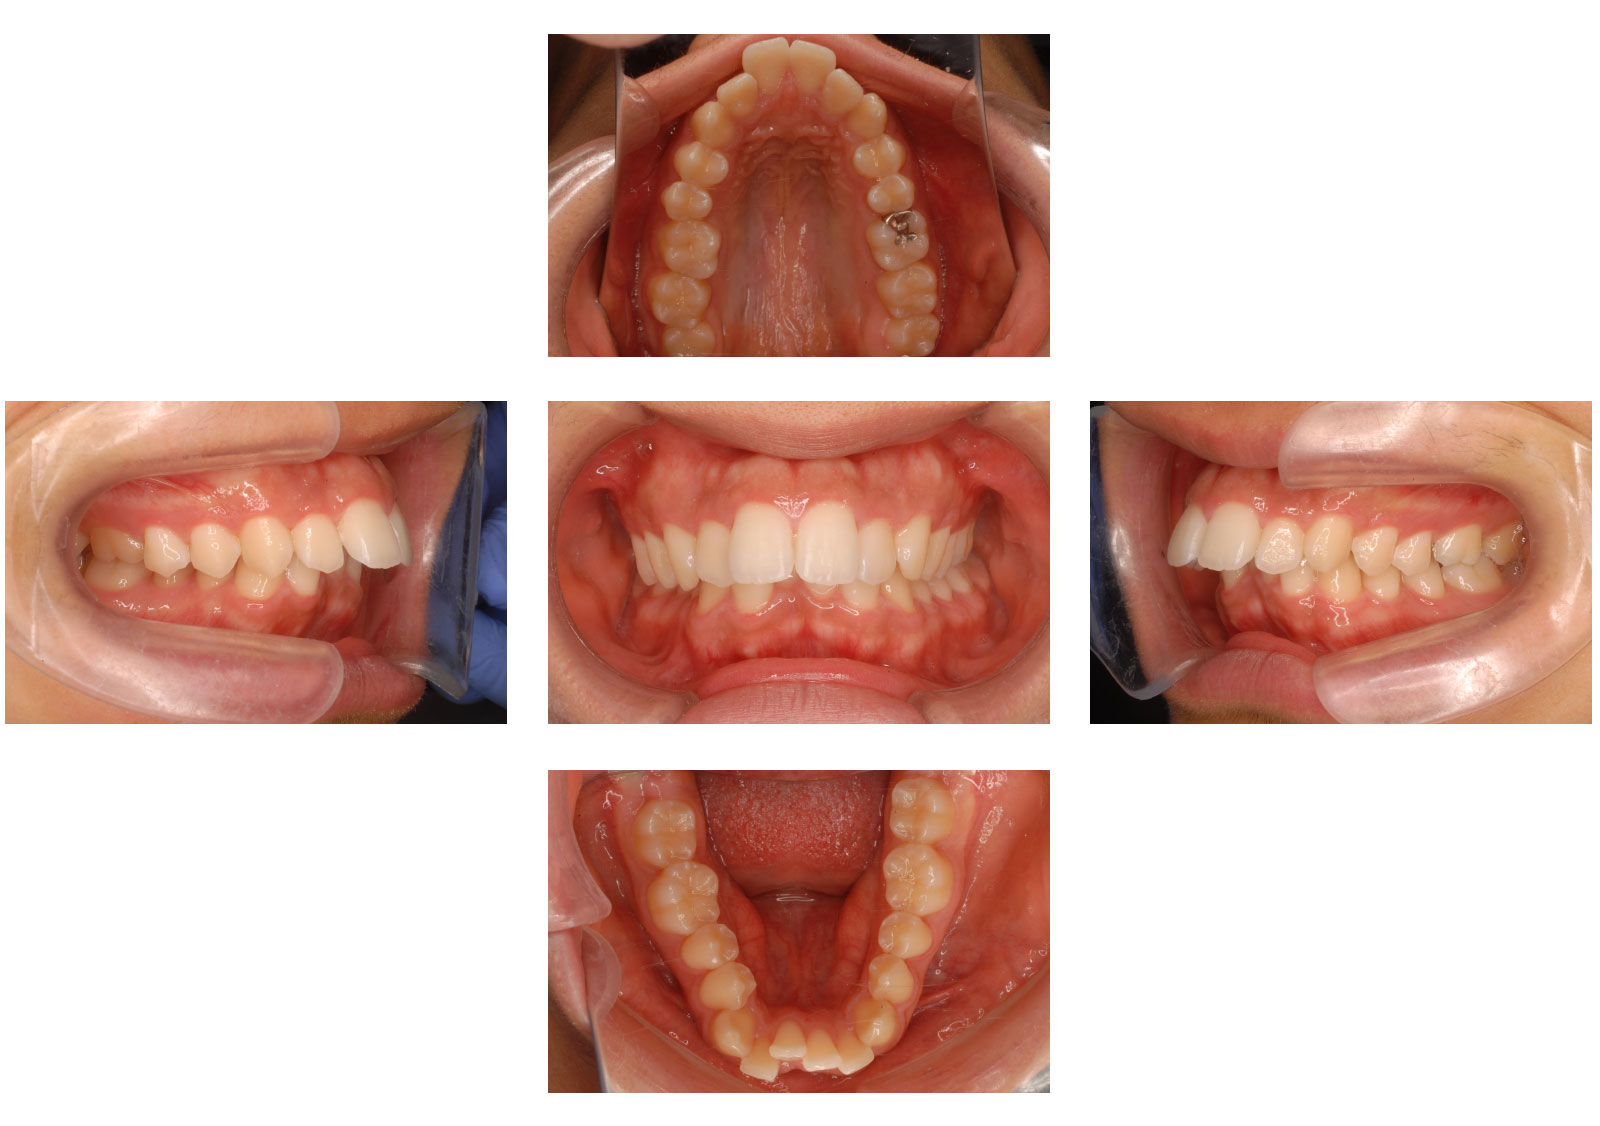

矯正後

症例画像